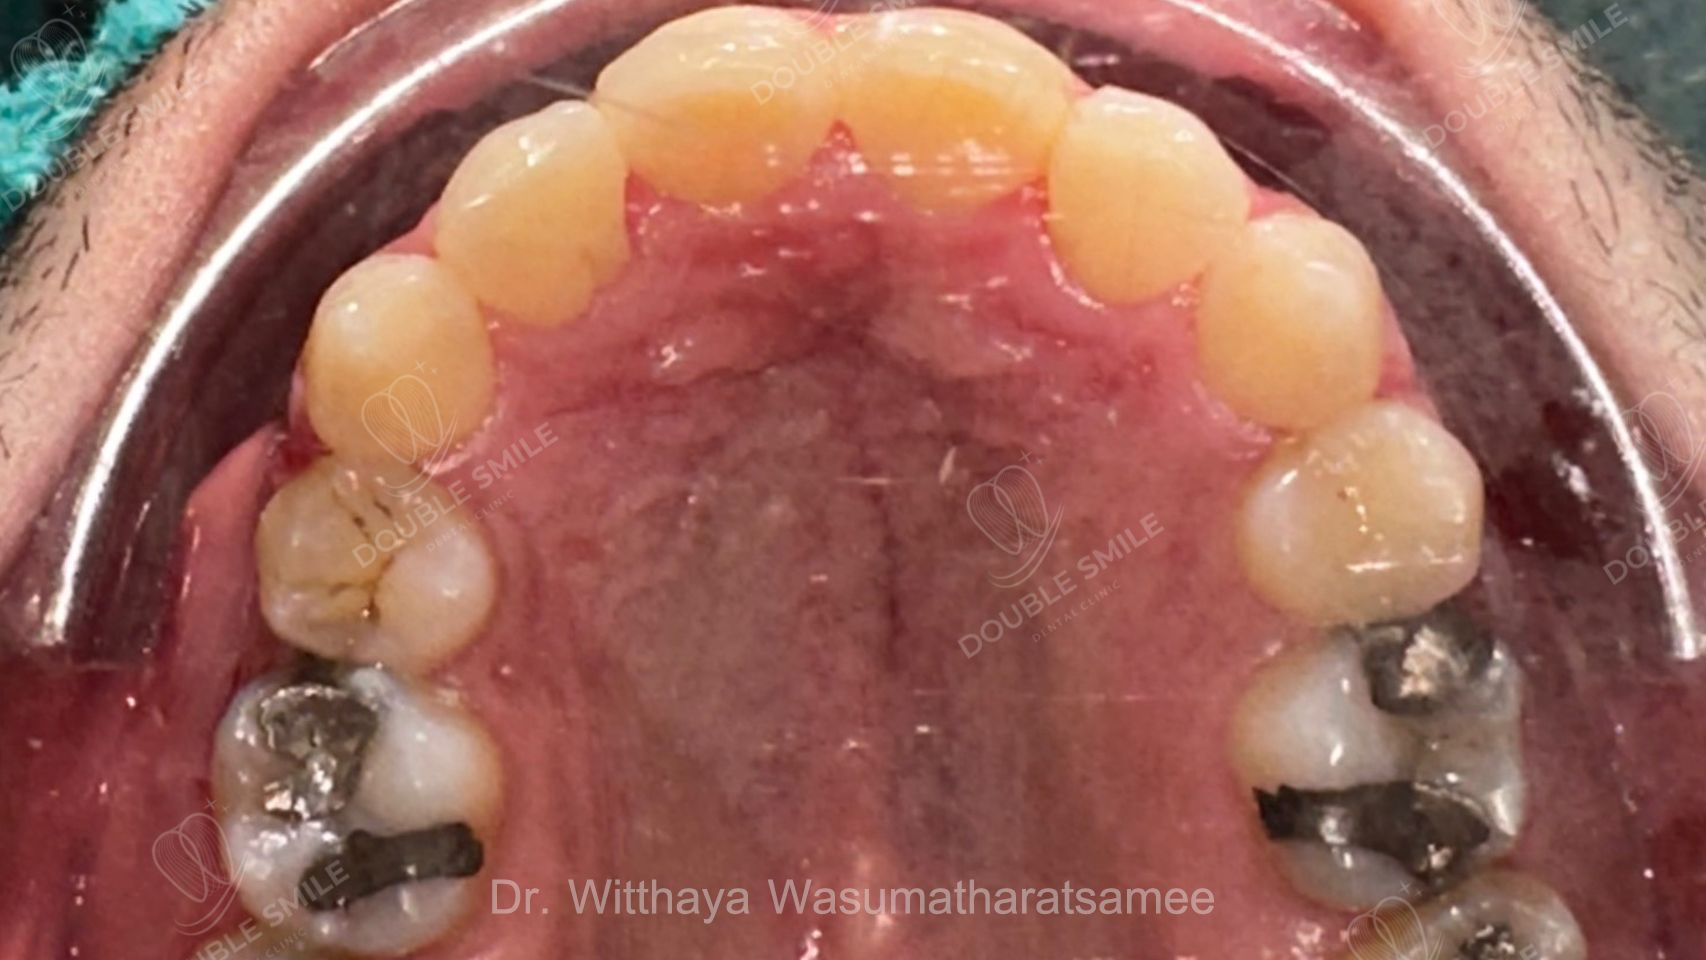

After

Case Review

Before & After